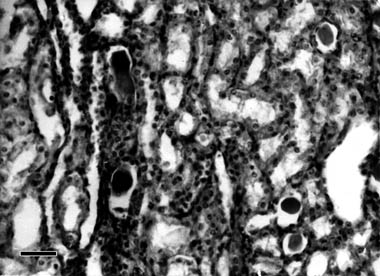

Histological examination of kidneys revealed granular or hyaline droplet degeneration, desquamation, as well small necroses. These were more pronounced in the epithelium of proximal convoluted tubules in cortex (Fig. 1) compared to the distal ones. In some regions of the cortex and medulla small haemorrhages and mononuclear cell infiltration were observed. Some of the glomerules were hypercellular, exhibiting slight endothelial or mesangial proliferation. The capillaries in the medulla were hyperaemic. Degenerative changes in proximal tubules were predominant in early stages (on the 10th day), whereas in later stages (on the 30th day) there was also slight proliferation of connective tissue and mononuclear cell infiltration in the interstitium, as well thickened basement tubular membranes, established by PAS staining. Granular and hyalin casts (proved by ironhematoxylin-Van Gieson staining) or proteinaceous debris in the lumen were observed in some convoluted or collected tubules (Fig. 2).

Fig. 2. Photomicrograph of kidney of sheep in group II. Group II was treated

per os with 6×7.0 mg of mercury in 1% mercuric chloride solution, slaughtered

on the 16th day of the experiment. Hyalin casts in the lumen of tubules.

H/E; 400 ×; bar = 25 µm.